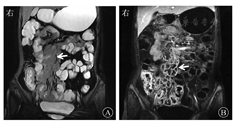

增强扫描增生肿大淋巴结呈环形强化改变,为结核最为特异性的表现,且较CT显示更清晰[14](图2)。